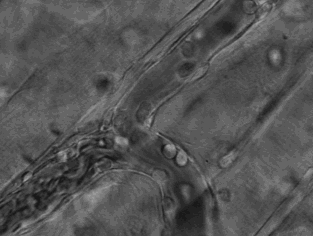

5.免疫細胞也可穿過血管壁奔赴“戰(zhàn)場”,向炎癥和創(chuàng)傷組織處進軍、圍剿。